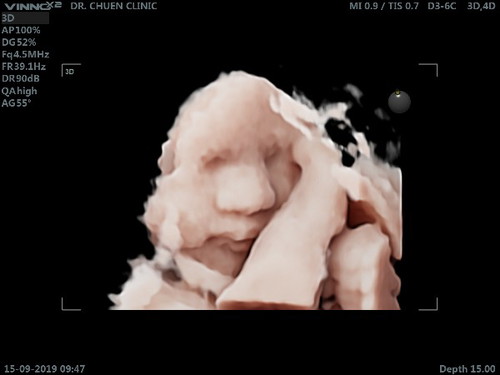

บ้านนี้ลูกชายค่ะ 32+4 week แล้วค่ะ

บ้านนี้35วีคค่ะ เพศชายค่ะแม่

ภาพชัดมากค่ะ😘

ปกติปิกหน้าตลอดเลยค่ะ ครั้งนี้เหนชัดสุด